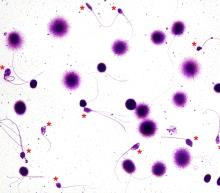

DFI آزمایشی است که در بررسی ناباروری مردان استفاده میشود. در این آزمایش میزان آسیب DNA در اسپرم مورد بررسی قرار میگیرد.

اسپرم سلولی است که در مرد تولید و پس از ترکیب با سلول تخمک در بدن زن جنین را تشکیل خواهد داد.

در تمام مردان درجاتی از آسیب به DNA اسپرم وجود دارد، اما هرگاه درصد این آسیب افزایش زیادی داشته باشد، باعث اختلال در حاملگی، ایجاد سقط و شکست در روشهای کمک باروری ( ازقبیل IUI ، IVF و ICSI ) میگردد.

در آزمایش DFI با استفاده از روشهای مختلف از قبیل SCSA ، TUNNLE ، SCD و سایر روشها، میزان شکست و آسیب DNA اسپرم بررسی و بر اساس درصد گزارش میشود.

این درصد نشان دهنده میزان اسپرم هایی است که دچار آسیب DNA میباشند. لذا هرچه این درصد بالاتر باشد نشان دهنده آسیب بیشتر به DNA اسپرم خواهد بود.

معمولا درصدهای کمتر از 30-25% خوب بوده و ایجاد مشکل نمیکند در حالیکه درصدهای بالاتر غیرطبیعی بوده و هرگاه بیشتر از 50% شود نشان دهنده آسیب بسیار شدید است.